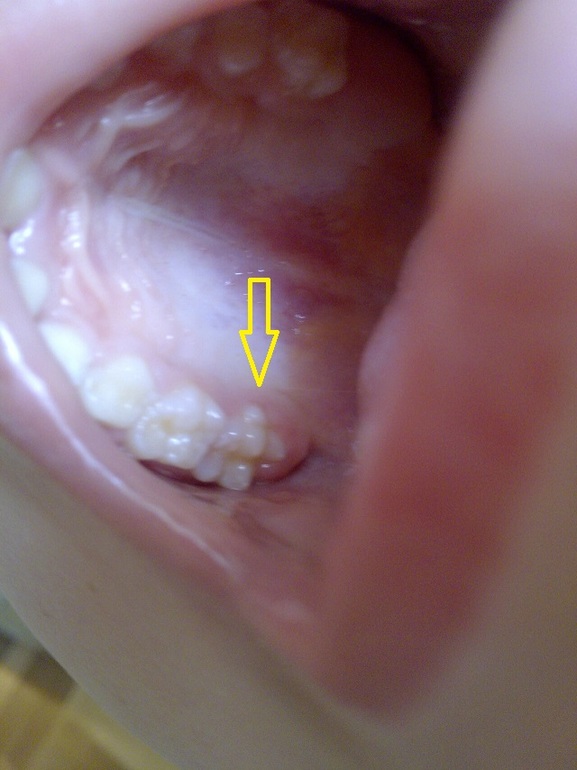

Странная форма зуба?

Здравствуйте. Моему сыну 5 лет и восемь месяцев. У него недавно вырос коренной зуб, странной формы , как будто "лишние детали" вокруг него. Скажите, что это? И что делать? Спасибо

Здравствуйте.Беспокоиться не стоит. Такая форма зуба встречается довольно часто. Это добавочный бугорок.